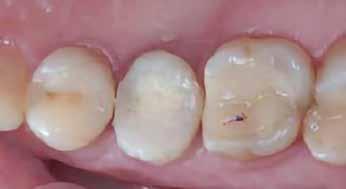

1. a–d. ábrák: Kiindulási klinikai állapot a két páciens esetében: Az első páciensnél a jobb felső premolárisok és az első moláris, a második páciensnél a bal felső második premoláris.

10. a ábra: Végleges lítium-diszilikát koronák. – 10. b ábra: Végleges monolitikus cirkónium-dioxid korona. – 11. a–b ábrák: Klinikai megjelenés tizenkét hónap elteltével. 12. a–b ábrák: Tizenkét hónapos kontrollröntgen-felvételek.